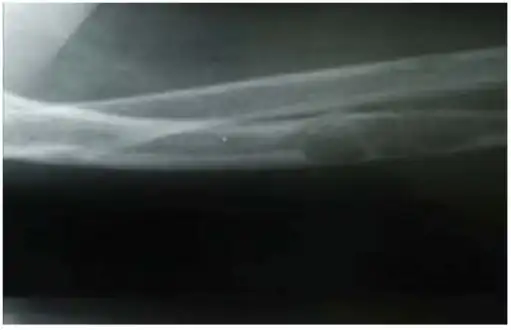

Lateral X-ray of the right radioulna showing osteitis fibrosa cystica lesion of ulna diaphysis with a pathologic fracture -

X-rays may also be used to diagnose the disease. Usually, these X-rays will show extremely thin bones, which are often bowed or fractured. However, such symptoms are also associated with other bone diseases, such as osteopenia or osteoporosis.[29] Generally, the first bones to show symptoms via X-ray are the fingers.[22] Furthermore, brown tumors, especially when manifested on facial bones, can be misdiagnosed as cancerous.[29] Radiographs distinctly show bone resorption and X-rays of the skull may depict an image often described as "ground glass" or "salt and pepper".[30][31] Dental X-rays may also be abnormal.[2]